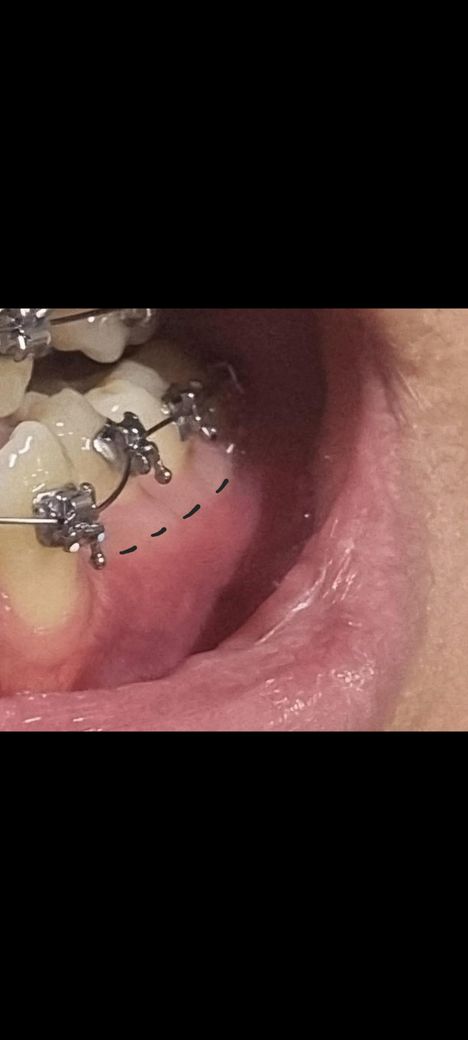

잇몸이 투톤(하얀색)인 이유가 무엇일까요..

사진처럼 잇몸이 투톤 ( 분홍+하양) 인데요,,

원래 잇몸 전체가 선분홍색이어야 정상적이고 건강한 잇몸 아닌가요?

제 잇몸 사진을 보시면 치아쪽 잇몸은 흰색이고 아래는 분홍색이네요.

현재는 교정 중이라 사진에는 교정기가 있지만, 교정 전에도

잇몸 색상은 나누어져있었습니다.

• 1번 째 사진

• 첫번째 사진에서 점선으로 경계지어진 부위 위쪽이 치은(부착치은)이고, 아래쪽은 점막 부위에 가깝습니다. 점막보다 치은이 색상이 더 연하고요 안쪽의 치조골이 좀 더 비쳐보여서 그런 색상이 나타나기도 합니다.

이와는 별개로 교정때문인지 잇몸 부종이 다소 관찰되긴 합니다. 평상시 잇몸관리를 위해 양치질을 꼼꼼히 해줄 필요가 있겠습니다.